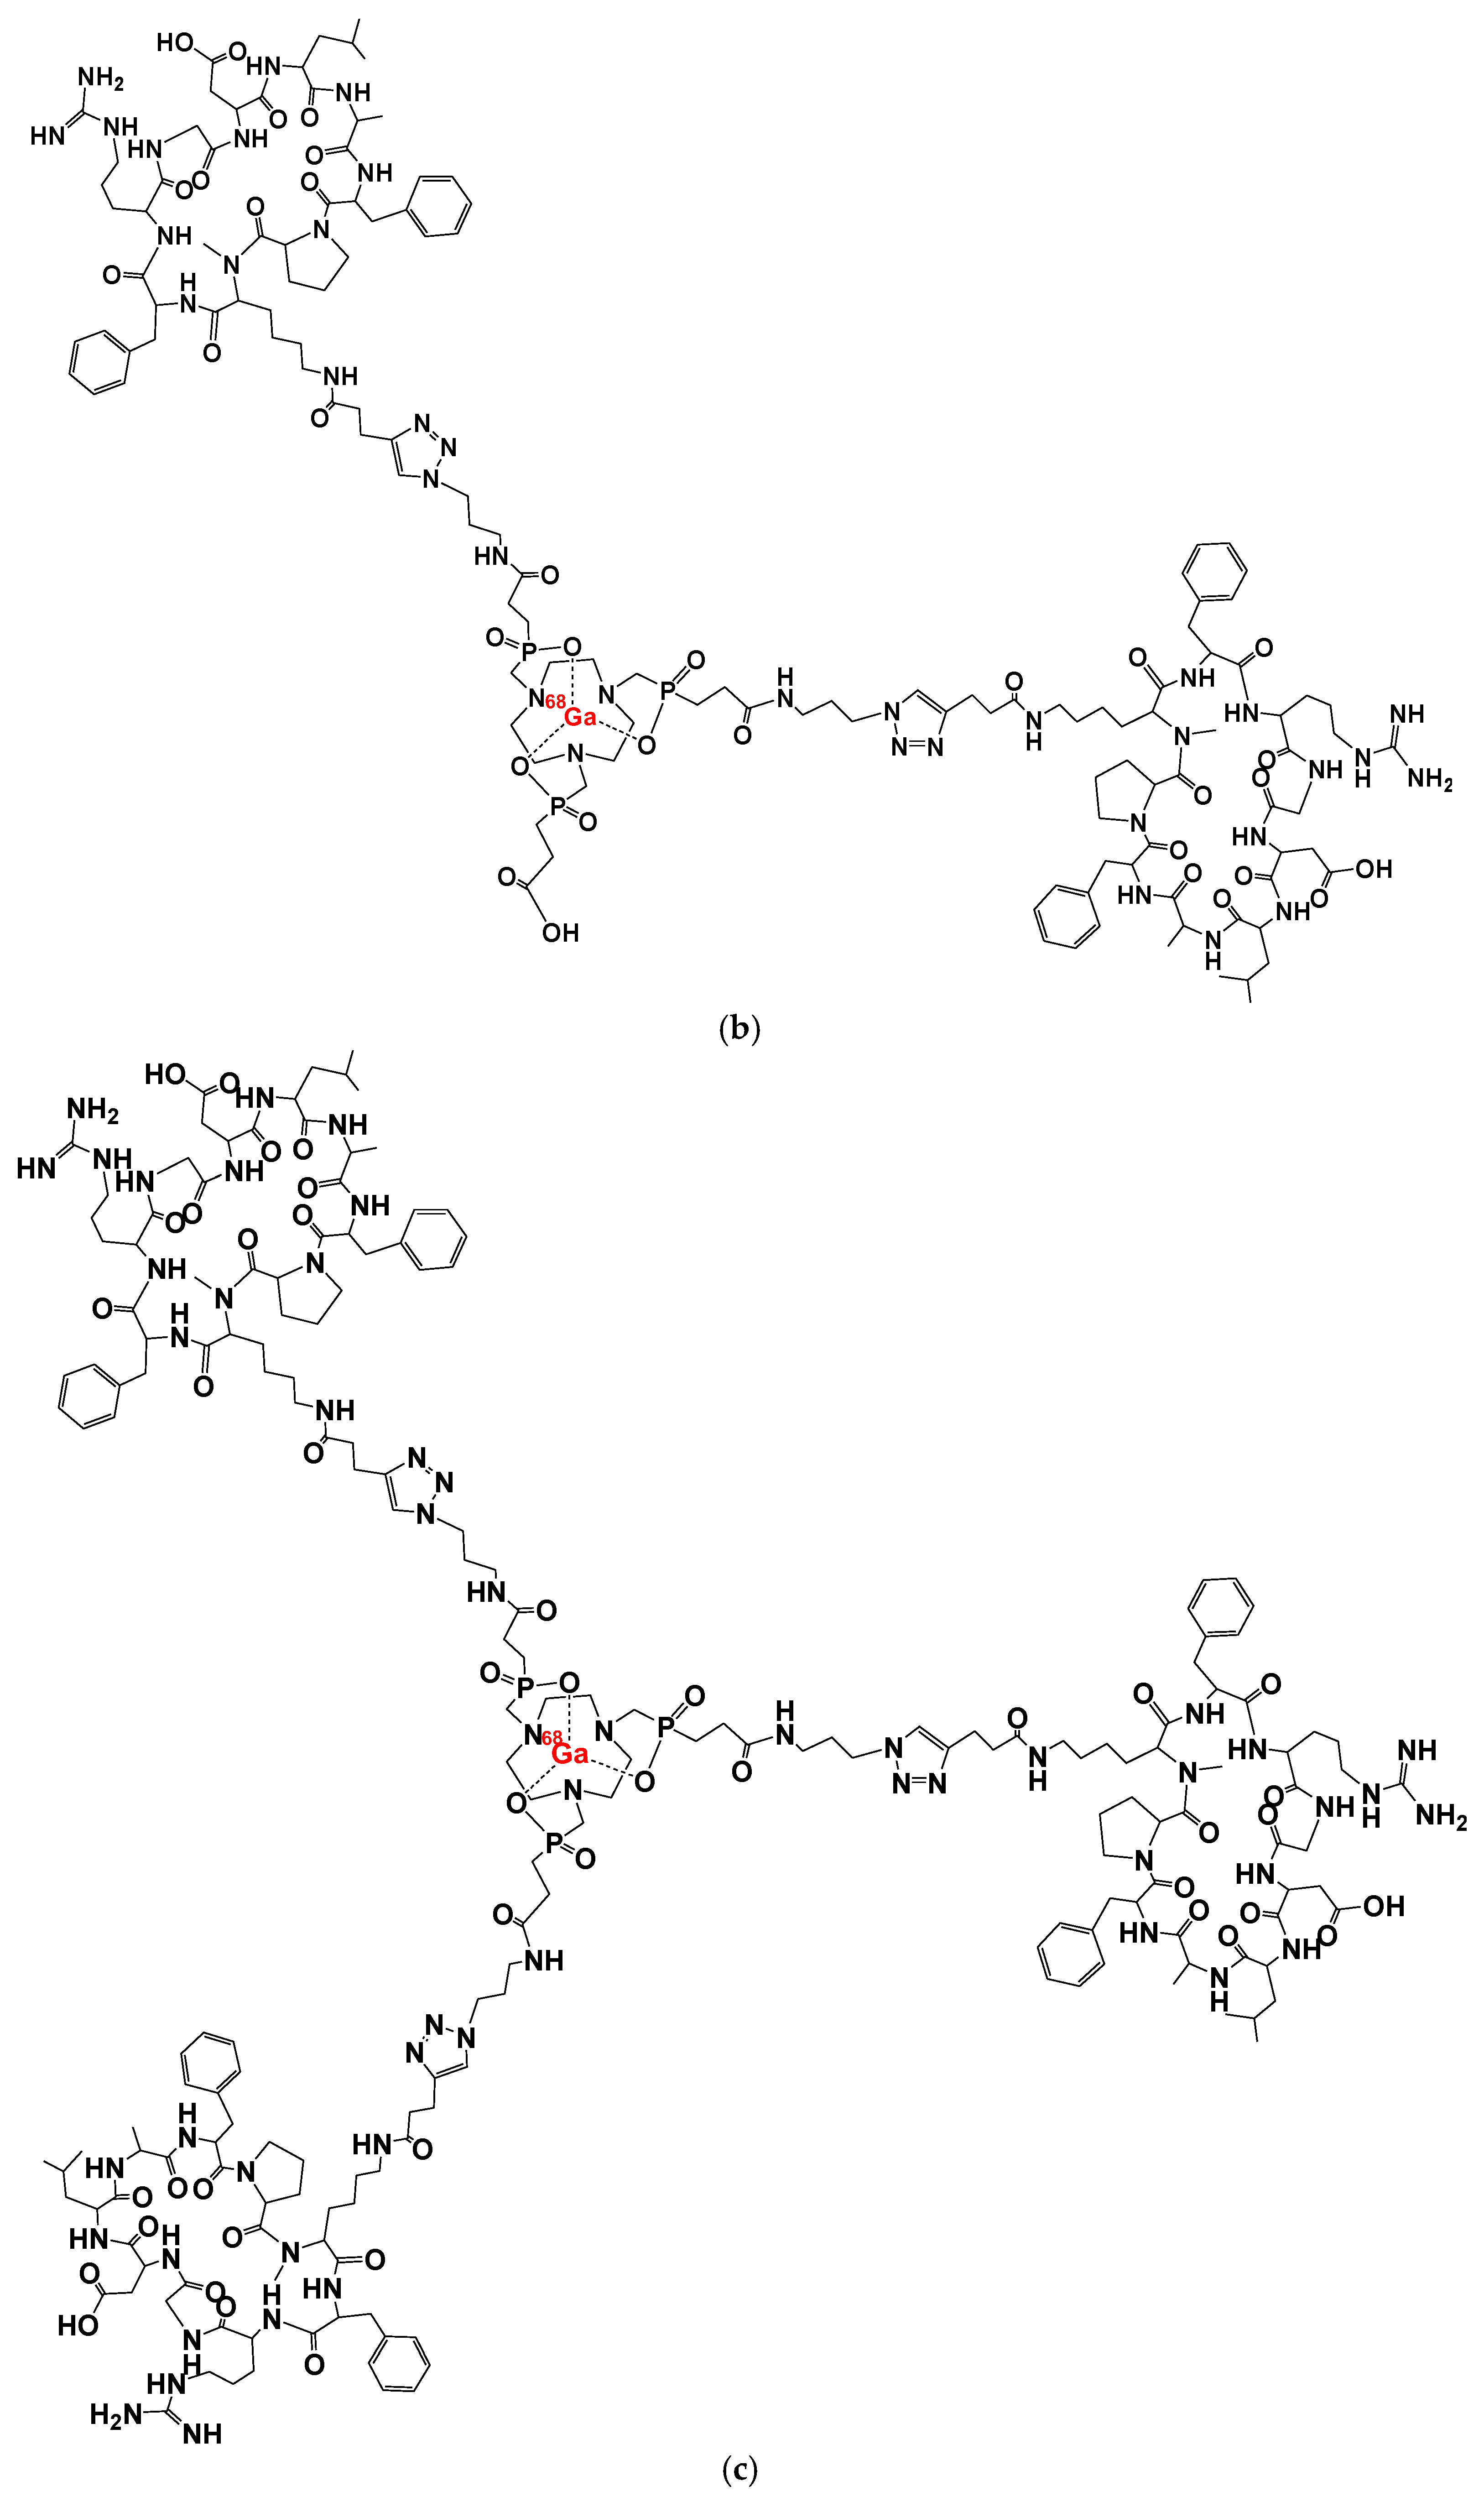

2. [68Ga]Ga-Trivehexin: A Radiochemical Insight